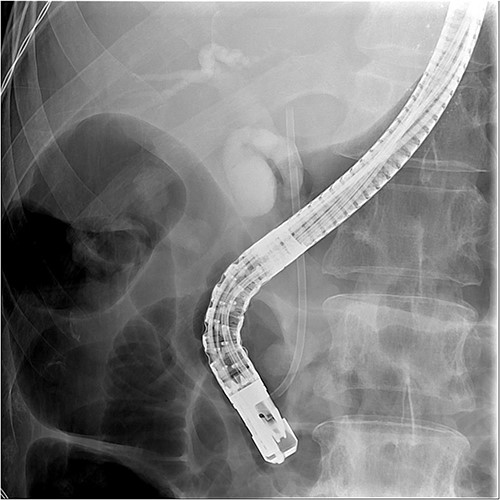

And then, a 7 French bostone scientific plastic stent was inserted over the guide wire for bile diversion. However, hemobilia was noted to be draining out from the stent right after. After reviewing the image, we realised that PVC was probably made (Fig. 3). After discussing with the general surgeon, we decided to arrange immediate surgical exploration to check for collateral damage and remove the CBD stones for cholangitis resolution. The stent was thus left inside for surgical guidance. Before the surgery, abdomen computed tomography (CT) was done and revealed retained contrast medium in the bile duct (Fig. 4) and malposition of the CBD internal stent with upper portion in the main portal vein (Fig. 5).

Just after ERCP, the abdominal CT showed retained contrast medium in bile duct.